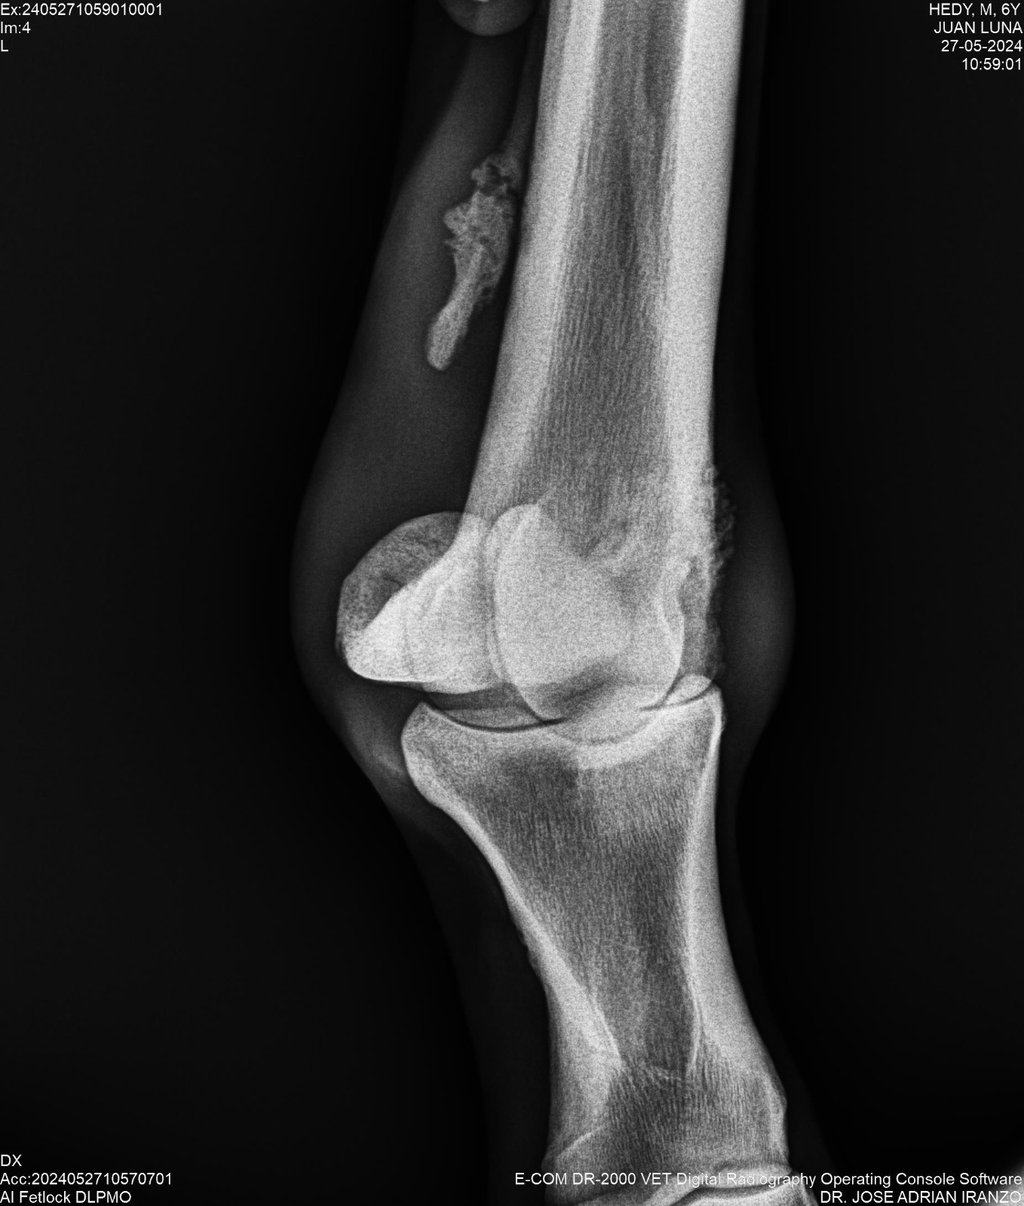

DIAGNOSTICO POR IMAGENES: ECOGRAFIA Y RADIOGRAFIA